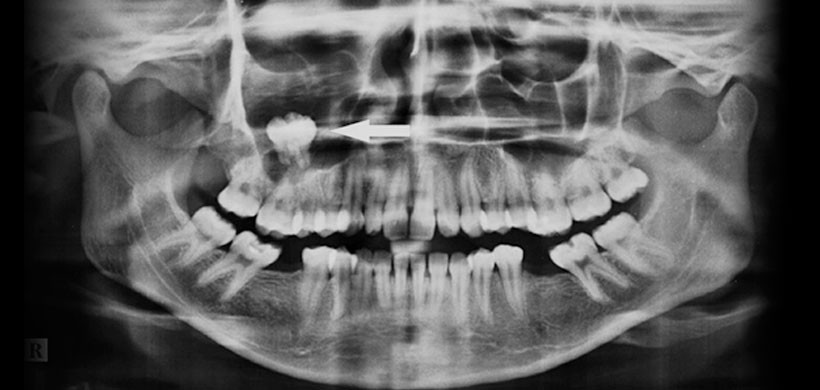

Se optó primero por realizarle una radiografía panorámica la cual muestra una radiolucides  que involucra el seno maxilar derecho junto con el tercer molar impactado (figura 1). Posteriormente se realizó una radiografía de senos paranasales para determinar que la piezas 18 este dentro del seno maxilar derecho (Figura 2) y finalmente se pudo comprobar mediante la tomografía computarizada y a su vez determinar el tamaño de la lesión así como las estructuras óseas y dentarias afectadas. (Figura 3)